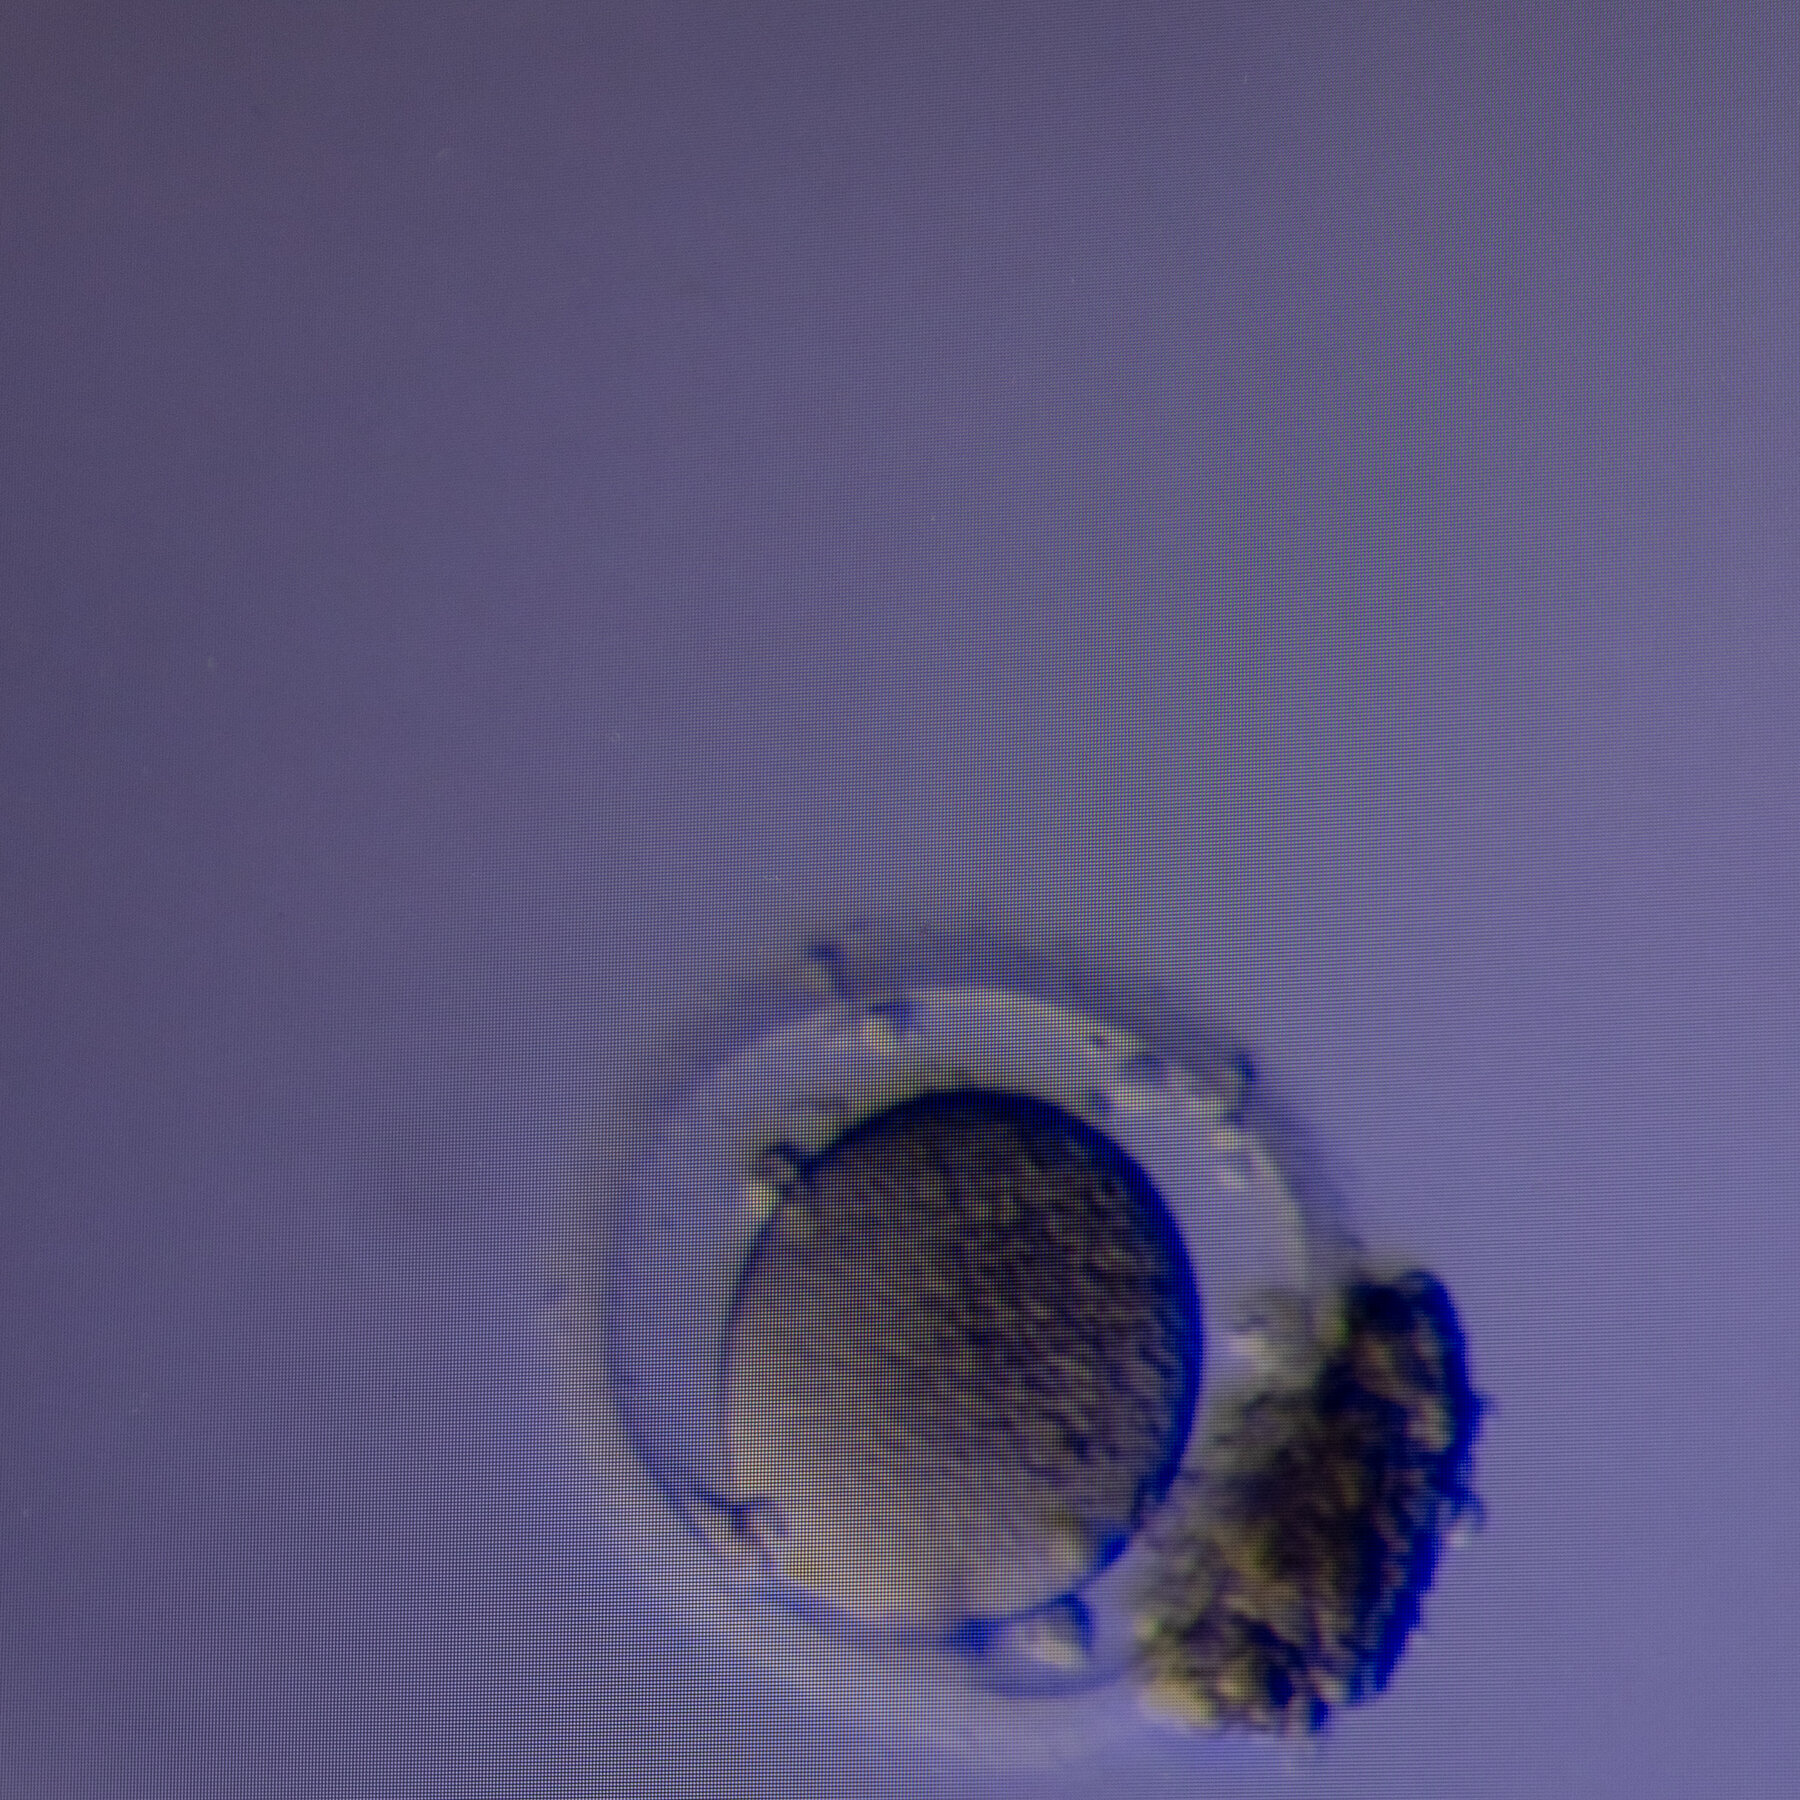

A study reported that the conventional method of searching follicular fluid didn’t find all the eggs. The new technology found extra eggs more than half the time.

New Method Can Find Hidden Eggs to Aid in Fertility Treatment

A study reported that the conventional method of searching follicular fluid didn’t find all the eggs. The new technology found extra eggs more than half the time.